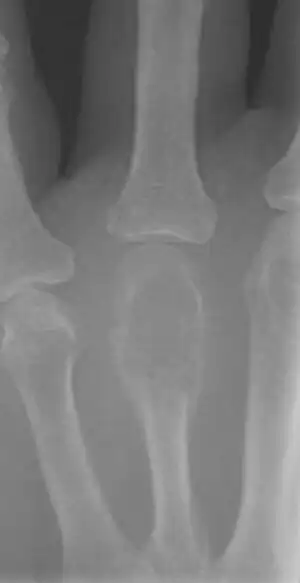

On X-ray, giant-cell tumors (GCTs) are lytic/lucent lesions that have an epiphyseal location and grow to the articular surface of the involved bone.[11] Radiologically the tumors may show characteristic 'soap bubble' appearance.[12] They are distinguishable from other bony tumors in that GCTs usually have a nonsclerotic and sharply defined border. About 5% of giant-cell tumors metastasize, usually to a lung, which may be benign metastasis,[13] when the diagnosis of giant-cell tumor is suspected, a chest X-ray or computed tomography may be needed. MRI can be used to assess intramedullary and soft tissue extension.

Front view X-ray one-year later it has grown